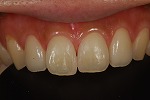

◆オールセラミック修復

~修復前~

オールセラミック修復

~修復後~

~修復後拡大~